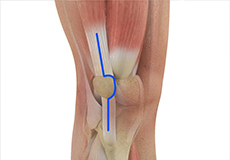

There are two major muscles in the knee - the quadriceps and the hamstrings, which enable movement of the knee joint. The quadriceps muscles are located in front of the thigh. When the quadriceps muscles contract, the knee straightens. The hamstrings are located at the back of the thigh. When the hamstring muscles contract, the knee bends.

Tendons of the Knee

A tendon is a tissue that attaches a muscle to a bone. The quadriceps muscles of the knee meet just above the patella and attach to it through a tendon called the quadriceps tendon. The patella further attaches to the tibia through a tendon called the patella tendon. The quadriceps muscle, quadriceps tendon, and patellar tendon all work together to straighten the knee. Similarly, the hamstring muscles at the back of the leg are attached to the knee joint with the hamstring tendon.